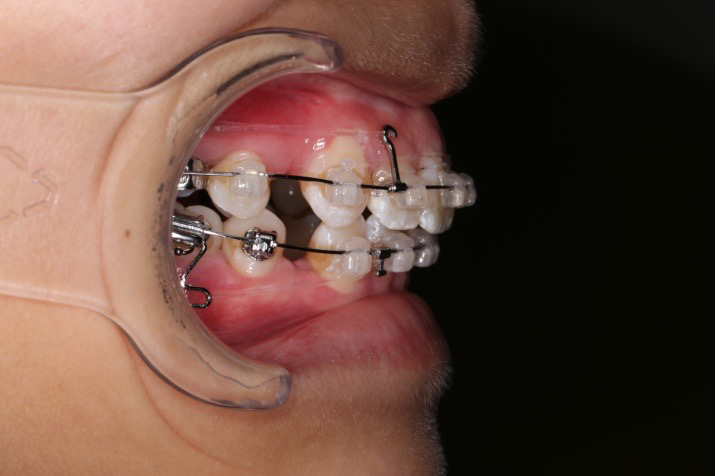

4.第6个月:2017.04.28 ◆ 上0.016*25ss 13/23v形曲,下0.017*25ss

5.第7个月:2017.05.26 ◆ 下颌36/46加power arm

2017.04.28

2017.04.28  上0.016*25ss 13、23近远中约5度 v形曲,下0.017*25ss

2017.05.26  磨牙近中倾斜,下颌36、46加power arm